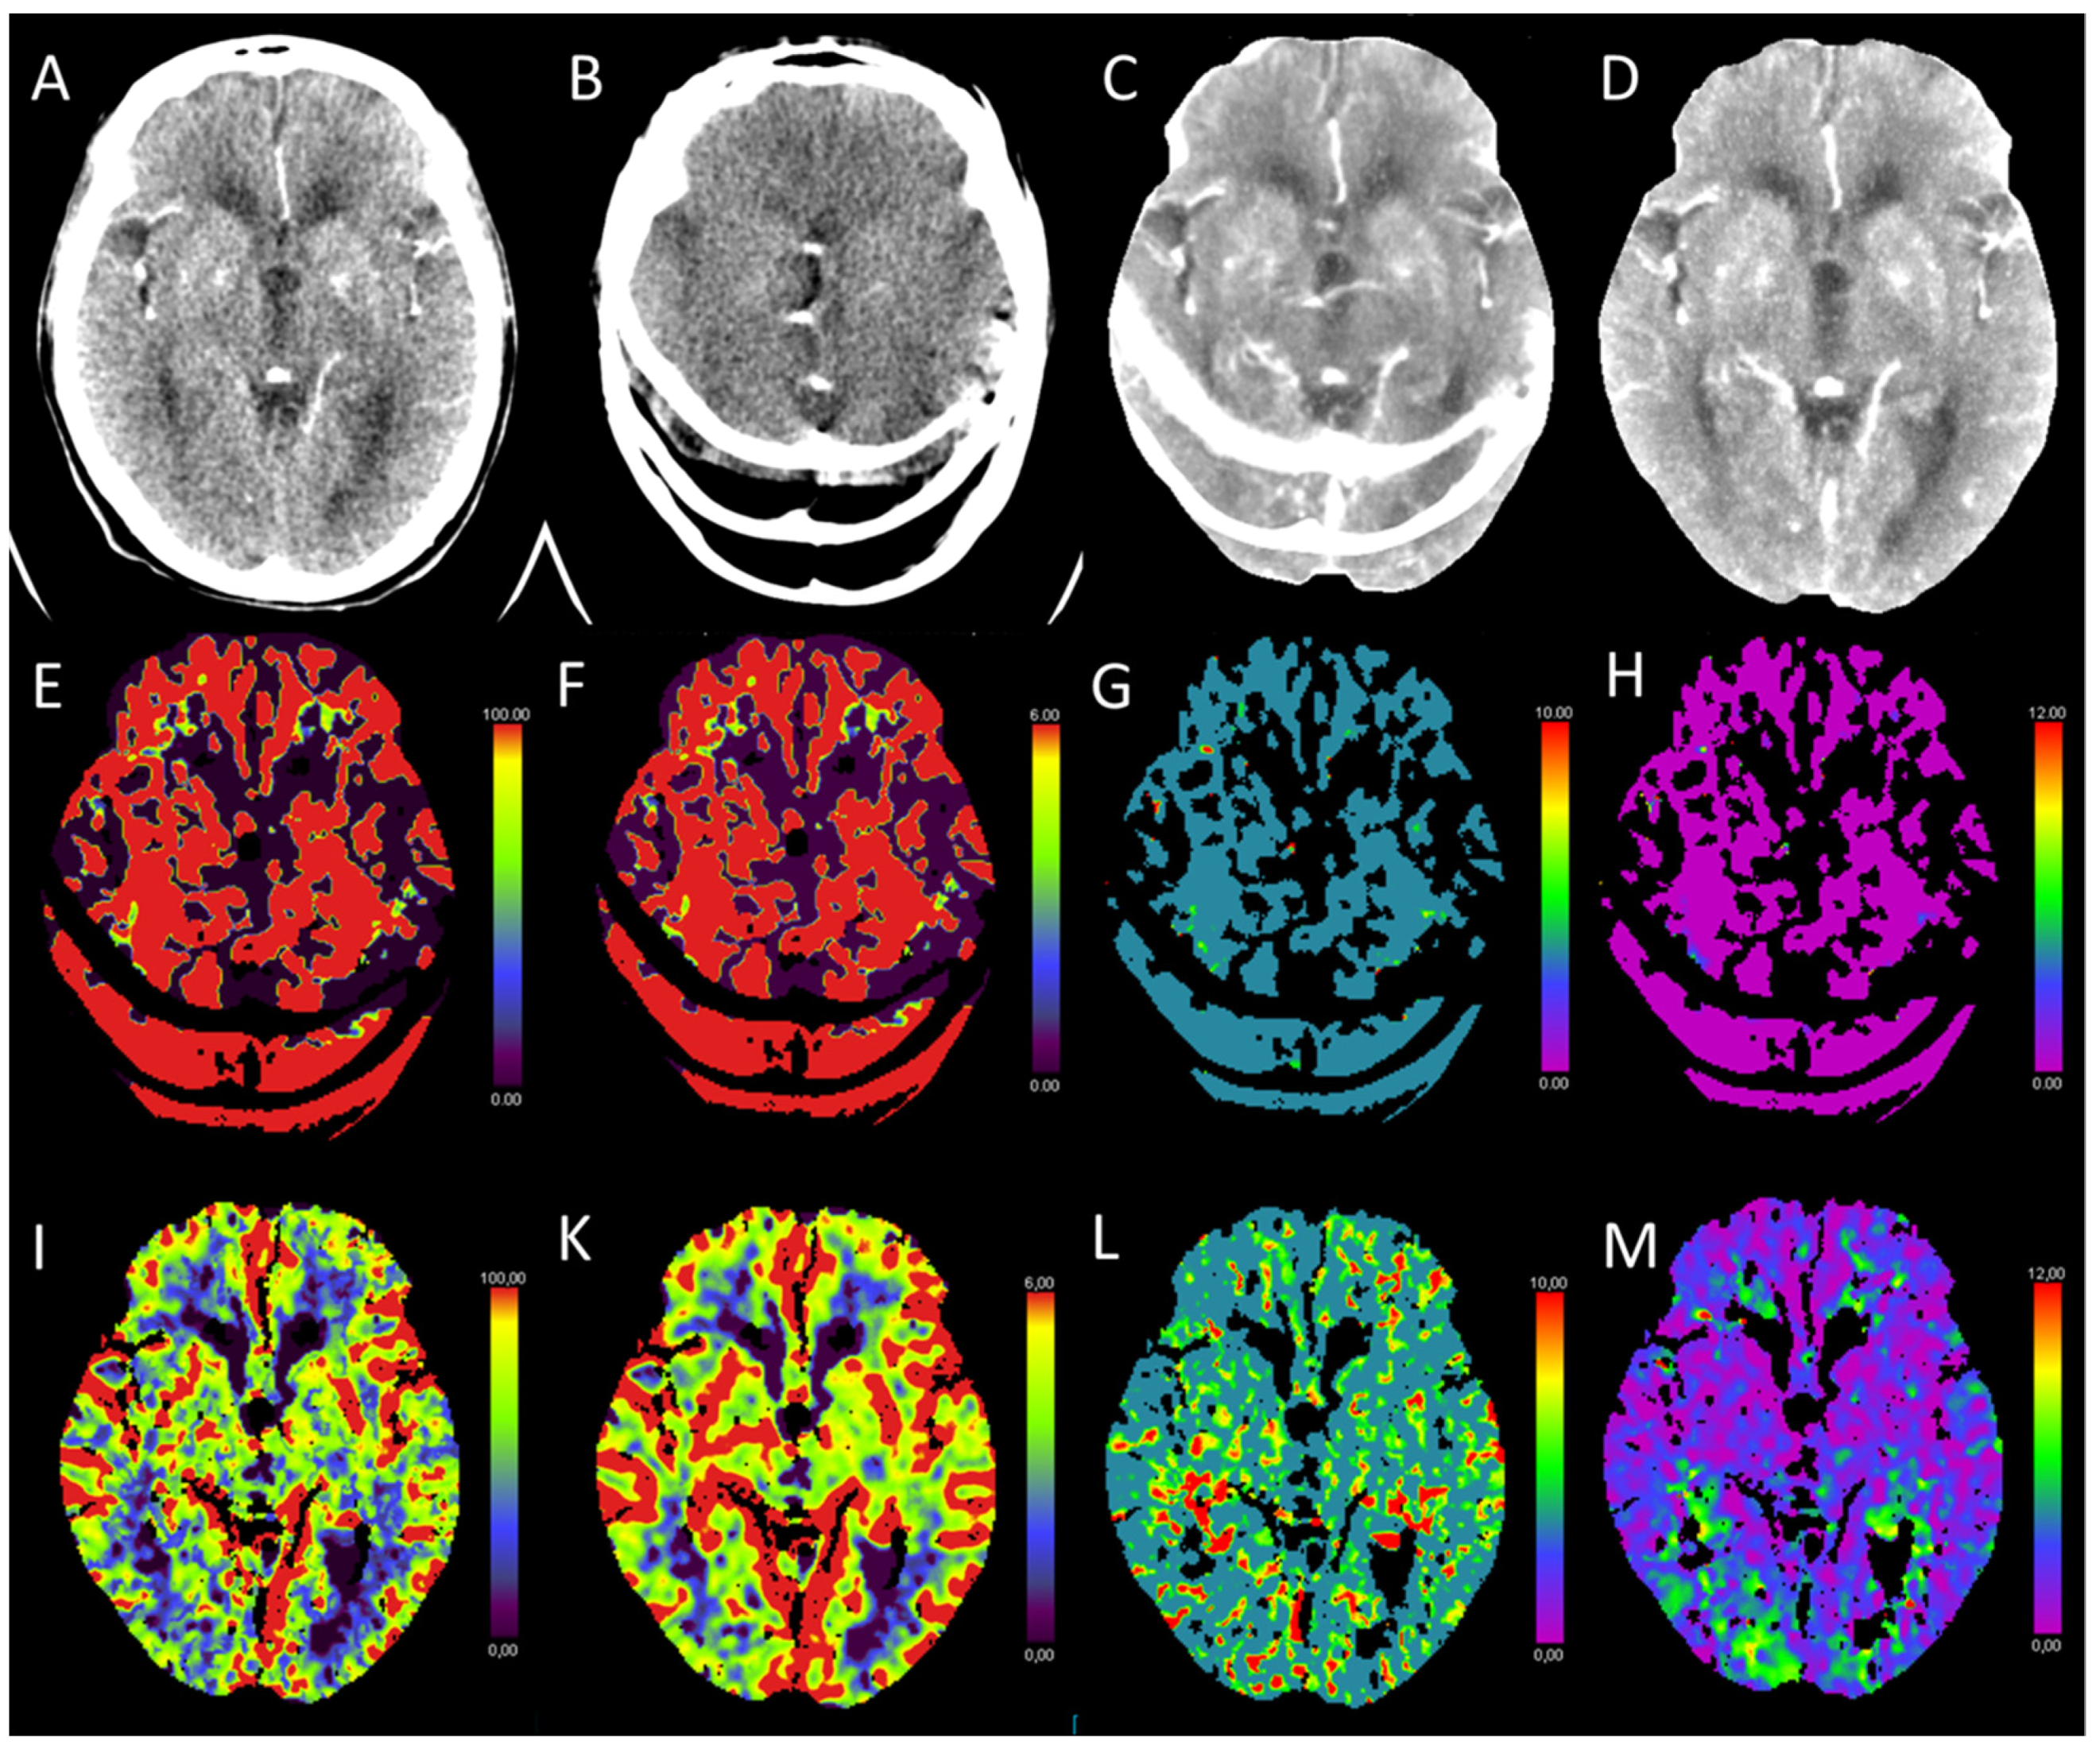

3.1. Acute Supratentorial Stroke

| Acute stroke | ↓ | ↓/- | ↑ | ↑ |